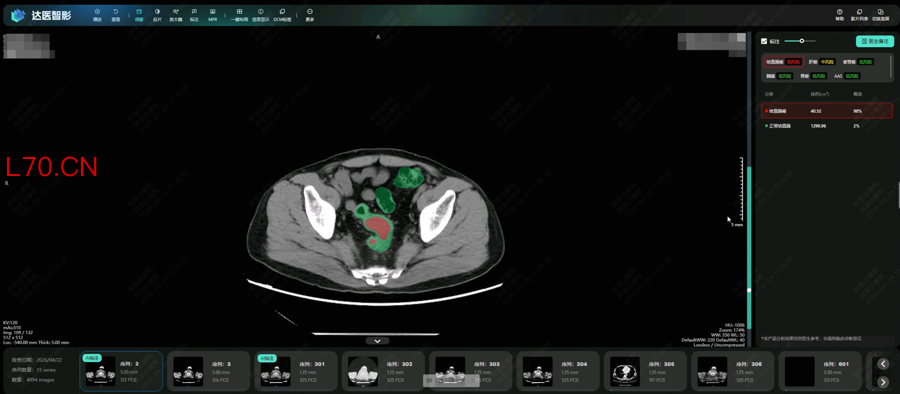

DAMO COCA模型自动识别结直肠癌风险

为此,达摩院发挥在“平扫CT+AI”方面的多年技术积累,采用“先定位、后诊断”的两阶段深度学习架构和混合监督学习策略,更针对小于3厘米的早期肿瘤专门训练,使得AI模型能精细分割形态复杂的肠道部位并克服内容物干扰,检测可疑病灶。

研究团队将AI模型部署在医院开展了两轮真实世界试验,共回顾了27433人的平扫CT影像,从中发现5例被遗漏的肠癌患者。其中一名患者曾连续两年拍摄平扫CT,均未检出肠癌,直到第三年通过肠镜确诊,此时肿瘤已发展增大。这意味着,AI模型可帮助类似情况的患者通过平扫CT更早发现异常,及时治疗。

“肠道病灶在平扫CT影像上极易被遗漏,而DAMO COCA这样的AI工具能有效帮助医生解决这一痛点,赋能临床诊疗,也帮助更多患者在无需肠道准备的情况下机会性发现健康隐患。”广东省人民医院放射科主任刘再毅表示,“未来,需要把AI模型部署到更多地区和机构,通过大规模的前瞻性研究,进一步获得高质量循证证据。”